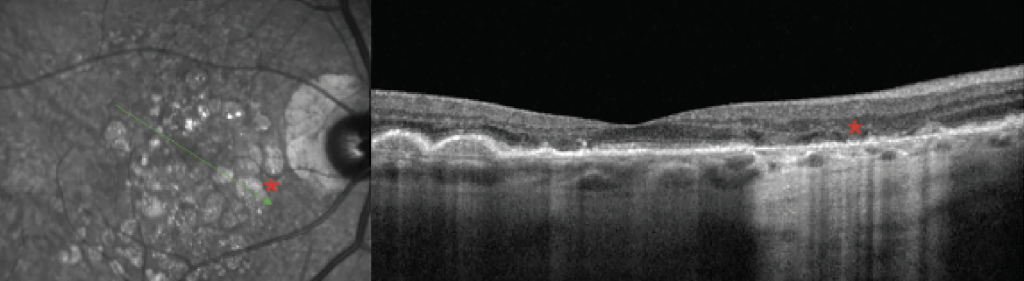

Las imágenes infrarrojas son un recurso valioso que puede ayudar a interpretar otras modalidades de imagen como OCT y FAF y a menudo pueden detectar enfermedad macular sutil como drusas tempranas o depósitos drusenoides subretinianos (anteriormente pseudodrusas reticulares), que pueden ser visibles en imágenes infrarrojas pero no clínicamente evidentes. Los informes de CAM también destacaron el uso de imágenes infrarrojas en DMAE para detectar GA ( Figura 6 ). Los hallazgos infrarrojos de GA se definieron como lesiones altamente reflectantes mayores de 250 µm con bordes bien definidos. 10 Mientras que las lesiones de GA son hipo-FA con FA de longitud de onda corta, aparecen tan brillantemente reflectantes con nIR ya que las longitudes de onda infrarrojas son fuertemente reflejadas por la esclerótica. Las longitudes de onda infrarrojas también tienen uso para resaltar lesiones maculares inflamatorias como las que se observan en la neurorretinopatía macular aguda, que aparecen como lesiones petaloides oscuras correspondientes a áreas de interrupción de la zona elipsoide observadas en OCT, pero pueden no ser clínicamente evidentes ( Figura 7 ). Estas imágenes también son útiles para detectar complejos neovasculares sutiles en la retinopatía diabética proliferativa que son difíciles de visualizar clínicamente sin angiografía con fluoresceína.

Si bien las imágenes infrarrojas tienen una alta sensibilidad para la detección de enfermedades degenerativas de la retina y la mácula, también se han utilizado para el diagnóstico de diversas afecciones sistémicas, como la neurofibromatosis tipo 1 (NF1). La NF1, una afección autosómica de herencia dominante, conduce a la proliferación de células de la cresta neural, lo que causa la formación de varios hamartomas y tumores. 14 Algunos hallazgos característicos de la NF1 son manchas café con leche, pecas inguinales, nódulos de Lisch en el iris y, recientemente, anomalías coroideas irregulares brillantes visibles con imágenes nIR del fondo de ojo ( Figura 8 ). Histológicamente, estas áreas eran grupos de melanocitos y se denominaron hamartomas melanocíticos. Estas anomalías coroideas en la OCT infrarroja, junto con los nódulos de Lisch, forman parte del criterio diagnóstico revisado para la NF1, que se actualizó en 2021. 15 Se cree que estas lesiones son visibles con infrarrojos debido a su alta concentración de melanina, que parece brillante con luz infrarroja. 14